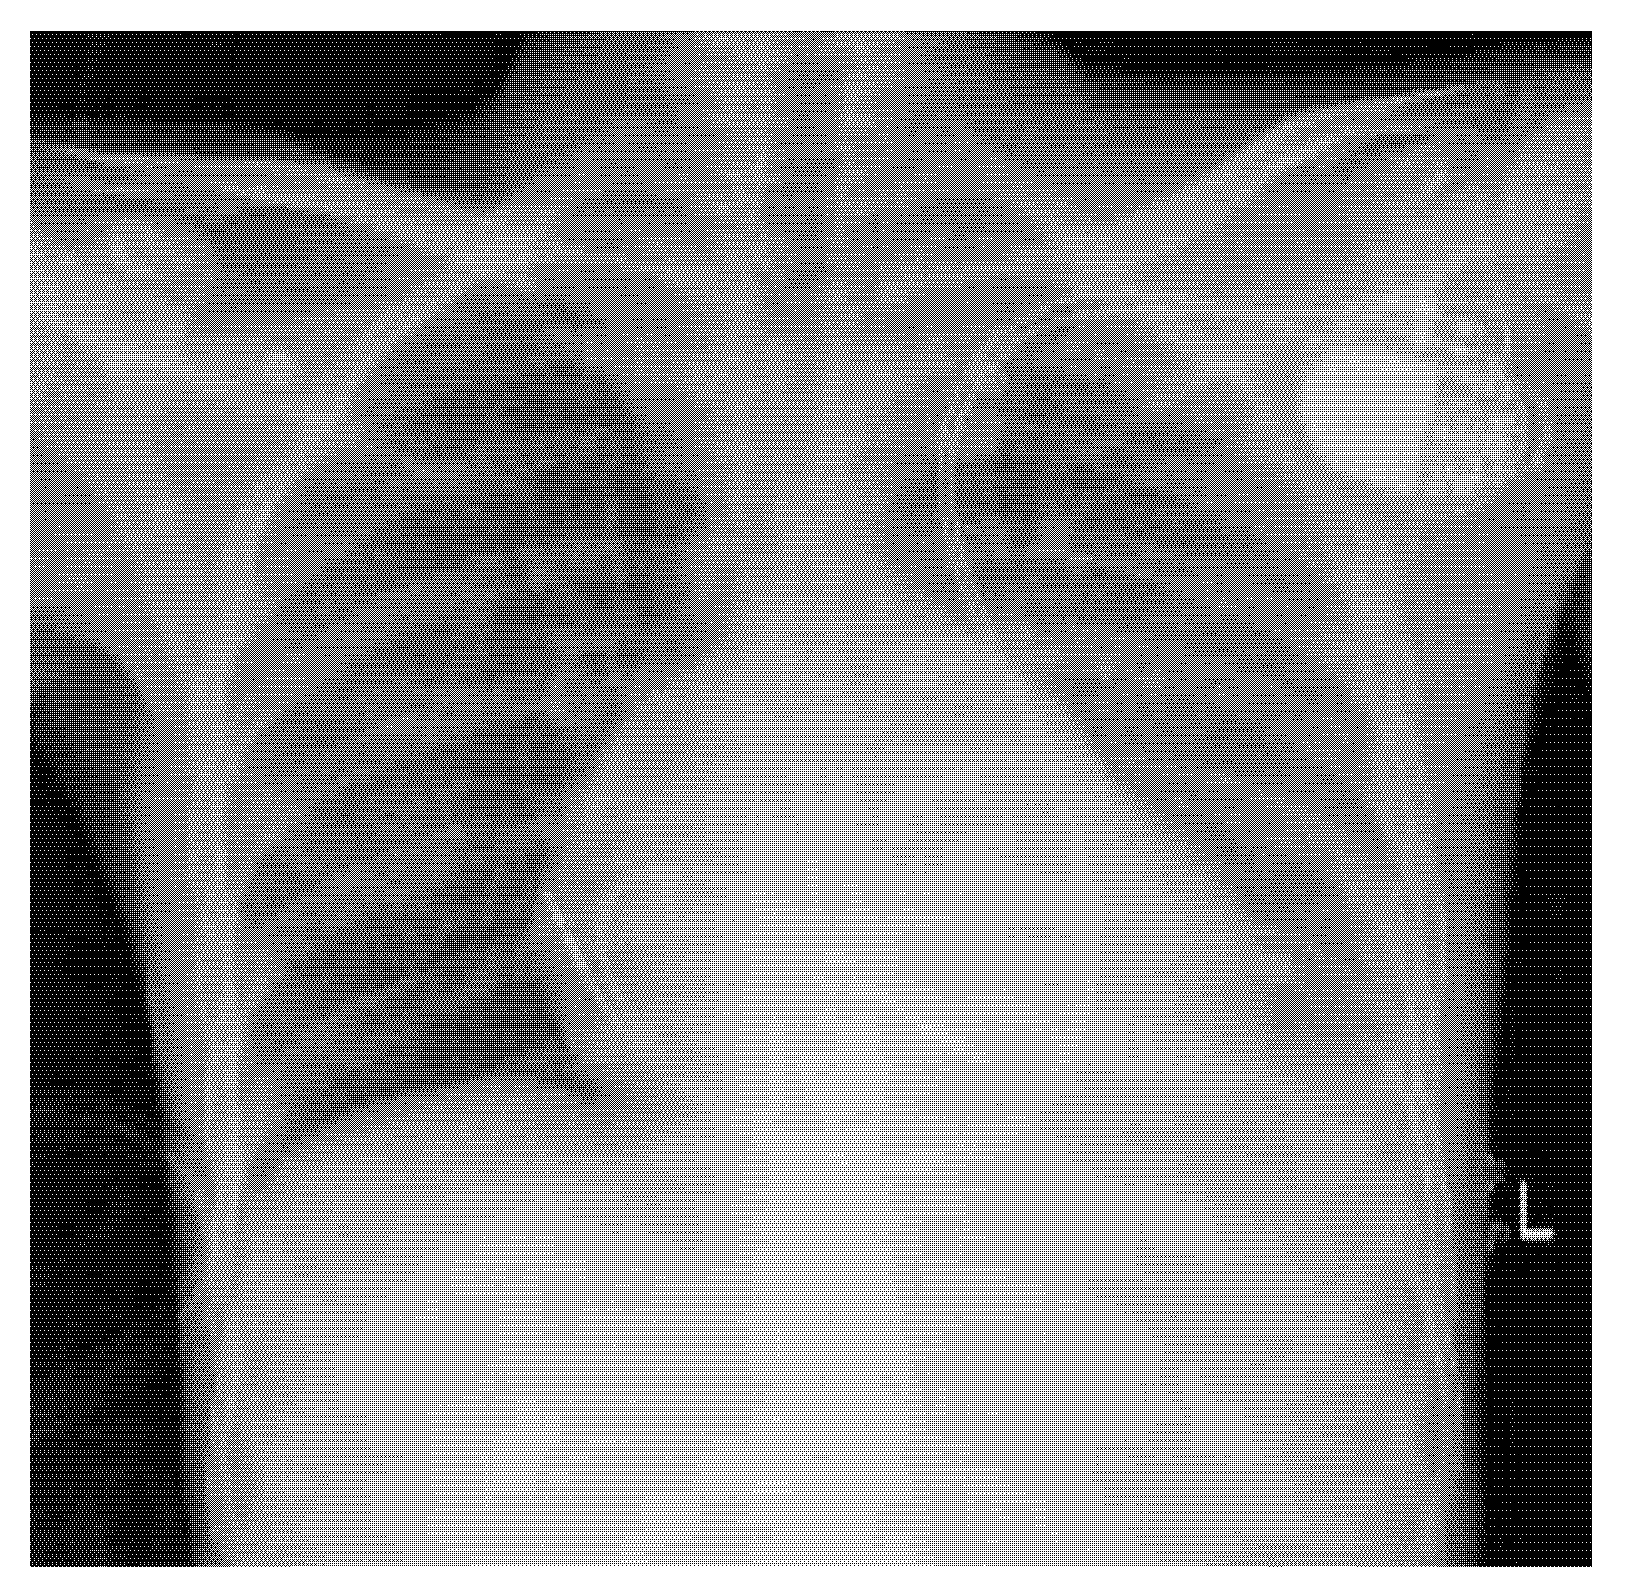

Further work-up was conducted to investigate the cause of CHB at a young age. Cardiac magnetic resonance (CMR) revealed epicardial enhancement affecting the basal and mid-anterior and anterolateral walls, with no late gadolinium enhancement and no regions of dyskinesia. Post-procedural chest X-ray confirmed stable and well-positioned dual-chamber PM leads with no immediate complications (Fig. 5).

Figure 5: Chest X-ray (anteroposterior view) depicting a dual-chamber pacemaker positioned in the upper left chest. The right atrial and right ventricular leads follow the trajectory of persistent left superior vena cava.